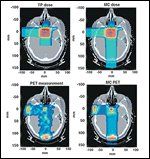

An interesting property of proton therapy is that positron emitters are produced within the body along the proton path that can be detected on a positron-emission tomography/computed tomography (PET/CT) scan taken after the fraction is delivered. As recently reported by Parodi et al,[29] PET scans produced images that were highly concordant with the actual dosimetry of the proton therapy.

Figure 4 shows the calculated doses for a pituitary adenoma treatment using orthogonal beams in the top panels compared to the measured and Monte Carlo–calculated doses from posttreatment PET scans in the bottom panels. The same are shown for a proton treatment with a single lateral field to the prostate in Figure 5. The dosimetric agreement between the PET measurements and the planned dose are not as good for the prostate as for the pituitary adenoma, likely due at least in part to motion and bladder filling. While there is further work to be done to account for these problems, this raises the possibility that PET/CT could be used to provide real-time dosimetric verification of prostate treatments in the future. This noninvasive method of verifying the delivered dose represents a form of quality control that would be quite unique in radiotherapy.

FIGURE 5

Comparative Doses for Proton Treatment of the Prostate